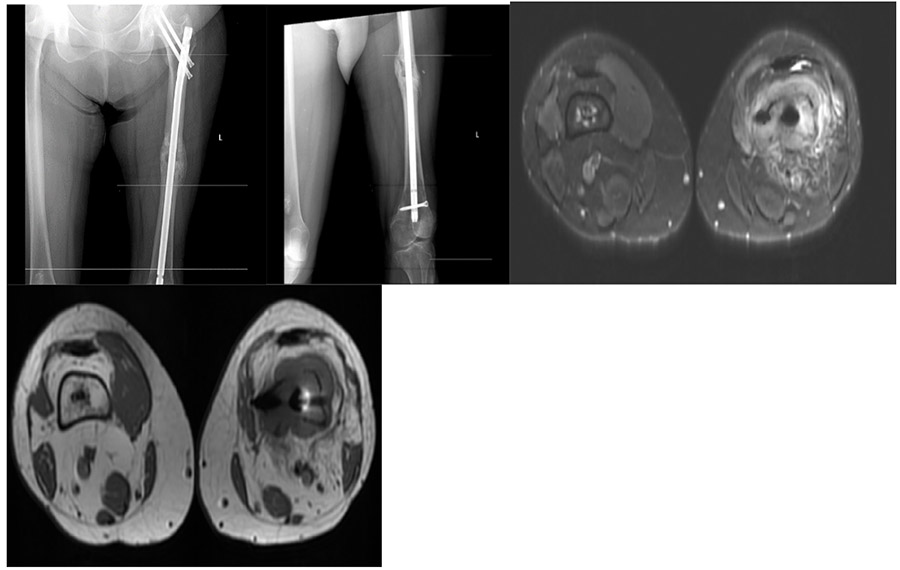

Follow-up: The X-ray shows bone healing after closed pinning due to a fracture. However, there is necrosis at the lower end. The MRI shows tumor tissue filling the lower end of the femur and extending beyond the bone.